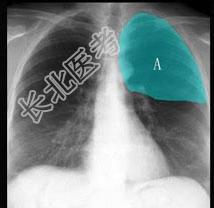

- 单项选择题在图所示正常胸部X线影像图像上,该英文字母所代表的肺段为 ( )

A、尖段

B、后段

C、尖后段

D、舌叶上段

E、前段